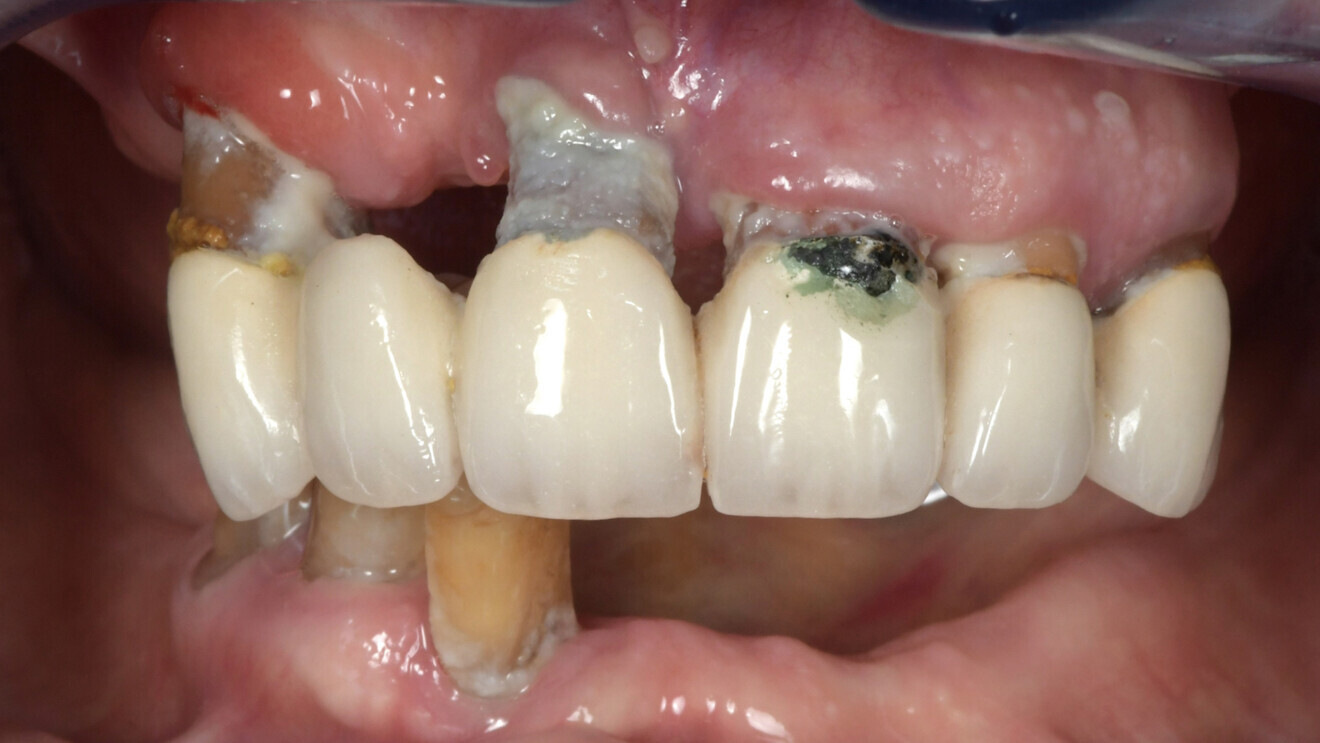

L’évaluation clinique a révélé un manque de soutien dentaire pour la lèvre inférieure et une récession gingivale significative autour du bridge maxillaire et des trois dents mandibulaires résiduelles (Figs. 1 et 2). Après examen clinique et radiologique (Figs. 3 et 4), la décision de réalisation d’une prothèse complète maxillaire et d’une réhabilitation fixe mandibulaire par implants est prise en accord avec la patiente.

Fig. 2 : Vue intra-buccale du bridge maxillaire (avec d’importantes récessions) et des trois dents mandibulaires résiduelles.